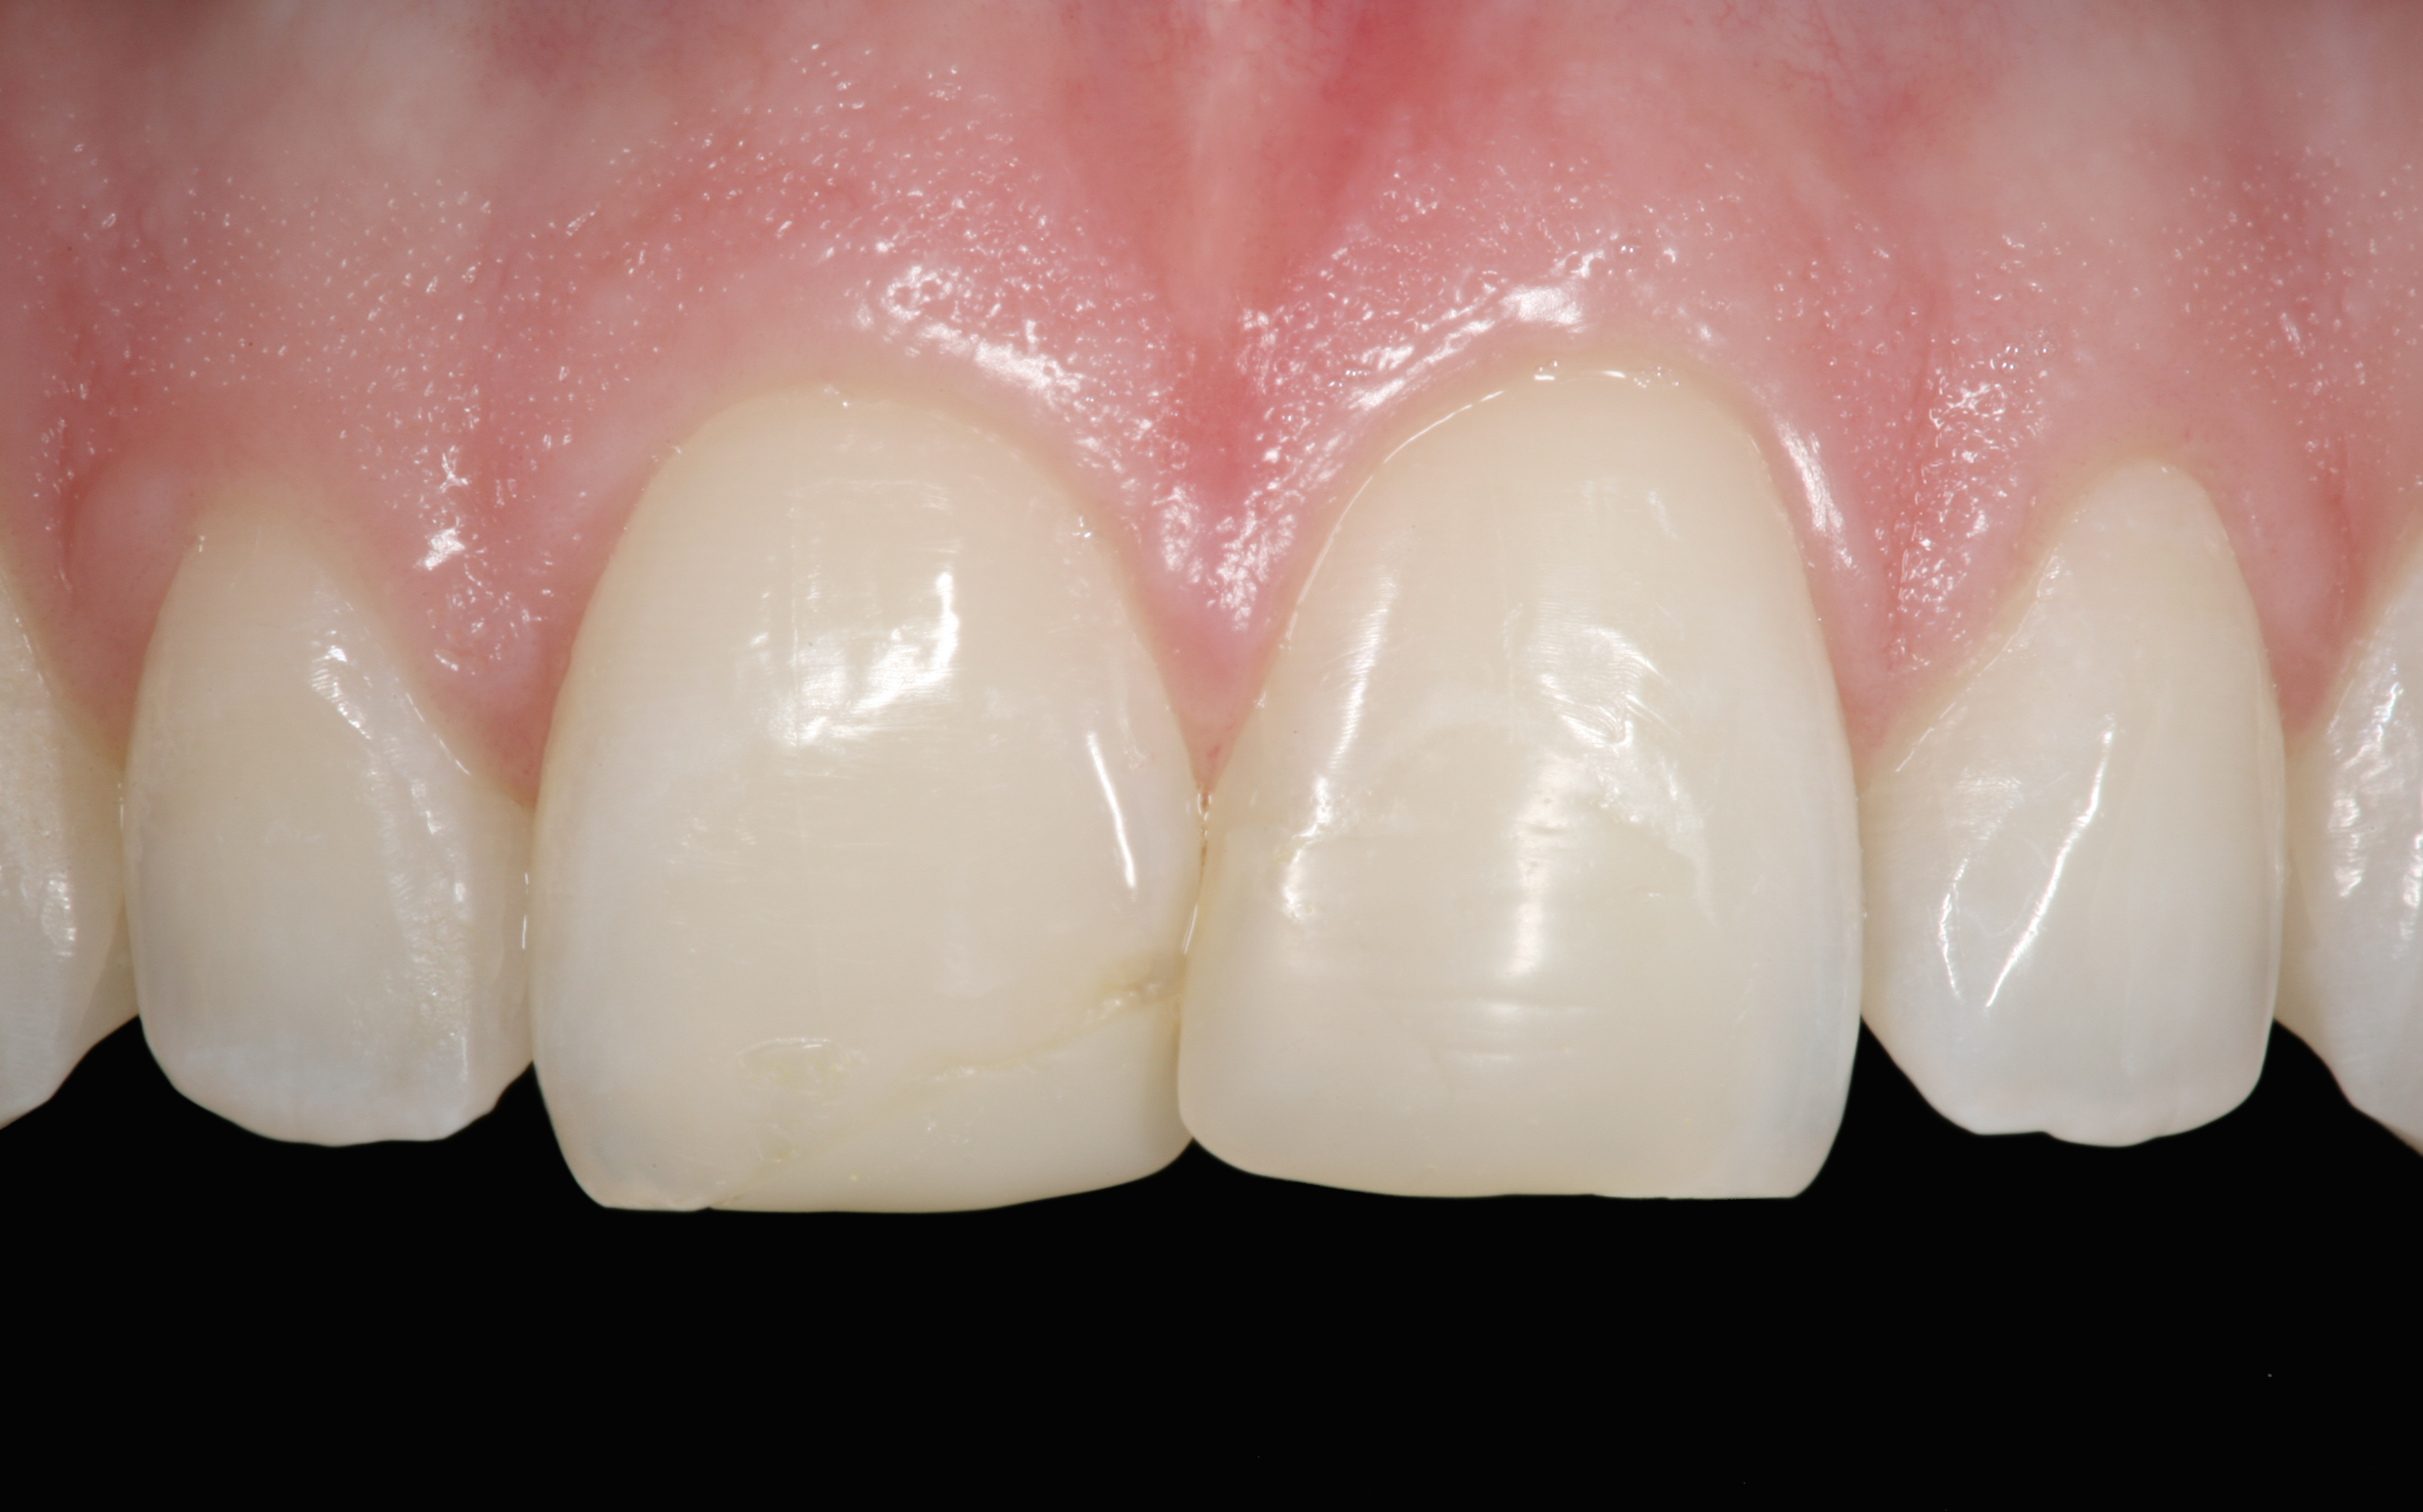

The clinical application of this protocol is illustrated in a patient situation where laminate veneers were placed on four maxillary incisors to replace lost tooth structure and restore function and esthetics. The failing restorations were removed, followed by a conservative veneer preparation (Figure 1 and Figure 2). The bonding surfaces of the feldspathic porcelain veneers were acid-etched with hydrofluoric acid for 2 minutes (Figure 3) and thoroughly rinsed. Then a silane coupling agent was applied (Figure 4). Figure 5 demonstrates the situation after bonding the veneers to the teeth with a composite resin luting agent.

The pretreatment situation.

Figure 1

Figure 13

The final restorative situation. (Restorative therapy by Dr. B. Wilk, Chalfont, PA.)

Figure 16